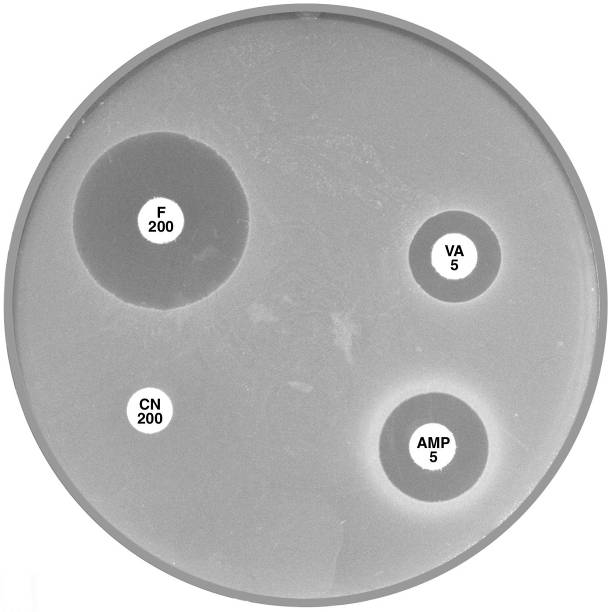

Plate 12.1.A Enterococcus faecalis and ampicillin The diffuse edge to the zone of inhibition > 4 mm around ampicillin (AMP 5) indicates susceptibility. |

Plate 12.1.B Enterococcus faecalis producing β-lactamase The sharp edge and the reduced inhibitory zone around ampicillin (AMP 5) indicate β-lactamase production and resistance. |